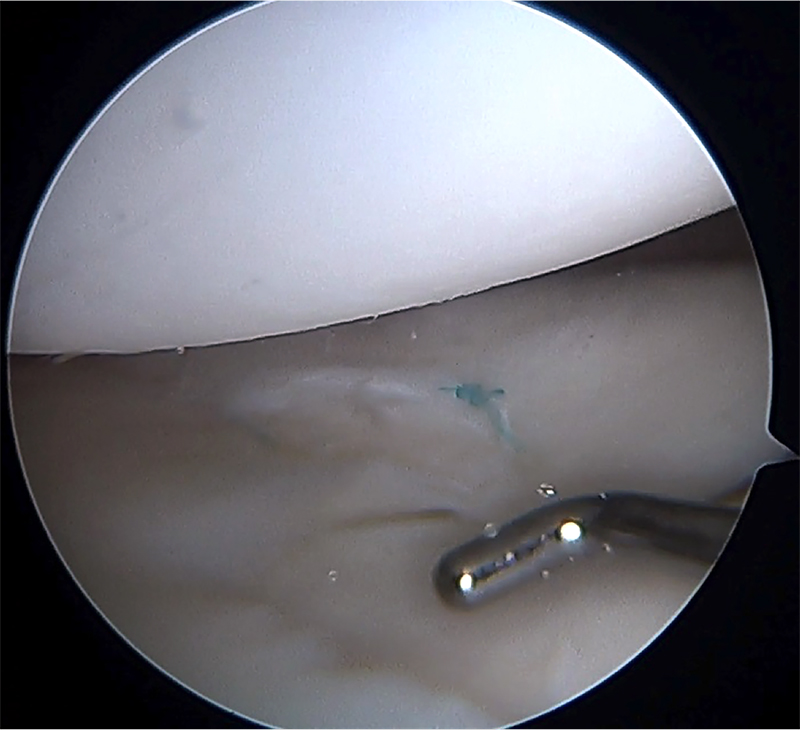

Terminada la reparación artroscópica (fig. 3) se elimina el líquido de la articulación y se procede a inyectar el PRP (fig. 4). Luego de esto se cierran los portales y dejamos al paciente con una férula con rango limitado (de 0 a 90 grados) para proteger la sutura en su fase inicial.

Figura 3: Rotura longitudinal de menisco lateral suturada.